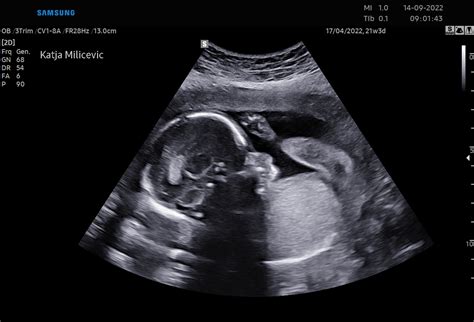

Otrokovo srce je zdaj dovolj razvito, da ga lahko zdravnik s klasičnim stetoskopom sliši tudi brez Dopplerjevega aparata. Z ultrazvočnim pregledom, ki ga običajno opravijo med 18. in 22. tednom nosečnosti, lahko ginekolog natančno pregleda otrokove okončine, notranje organe, srčne prekate in obe možganski hemisferi. Na tem pregledu je pogosto mogoče izvedeti tudi spol otroka.